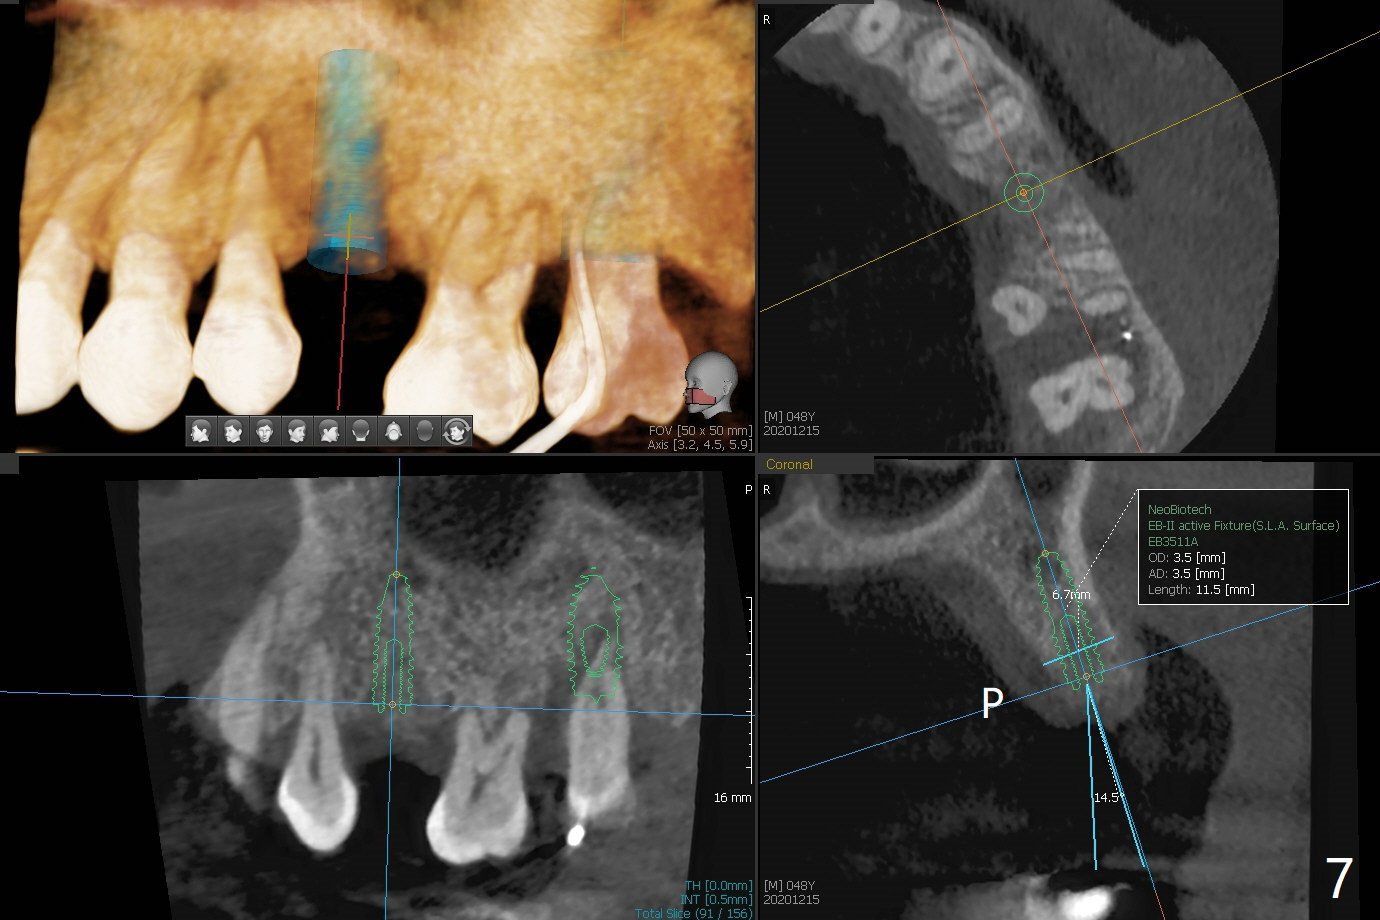

48岁女,严重牙周炎,要求拔除左上5松动牙(图一),经过劝说同意位点保留(图二)。在软组织(厚)区的骨粉(*, cortical, pressed collagen plug, perio dressing)以后帮助植牙?没毛病,不久就会吸收了,多可少,少不可多,大可小,小不可大。Steven

术后二周牙周敷料松动,取出后,伤口尚可(图三)。可能病人用右侧咀嚼,造成右上两个双尖牙松动疼痛,拔出后即刻种植修复,之后她能在右侧咀嚼,而食物撞击左上拔牙创疼痛,无法吃饭。术后三个月左上7疼痛,瘘道,插入牙胶尖(图四:*),根周阴影。其实腭侧根纵裂(图四,五:<),三个月已经发生(图二),可以即刻种植(图六),与5延期种植同时进行,使用导板。